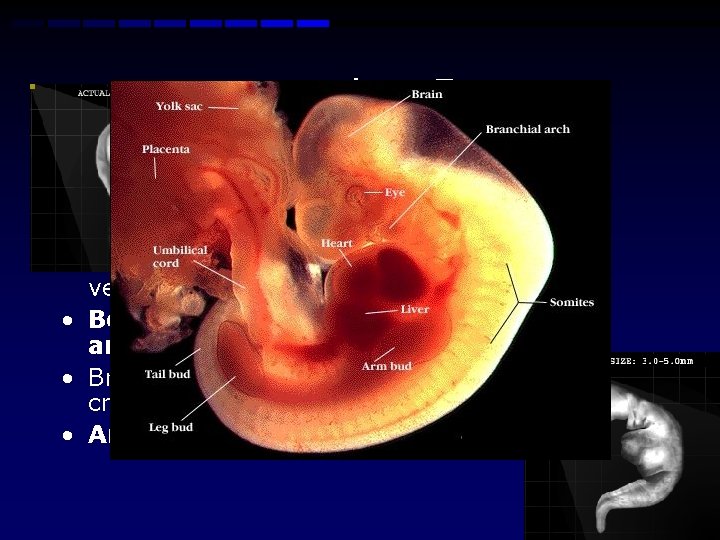

Week 4 -5 • Beginning of vertebra and bones • Development of the heart which now beats at a regular rhythm • Movement of basic blood through the main vessels • Beginning of the structures of the eye and ears • Brain develops into five areas and some cranial nerves are visible • Arm and leg buds are visible